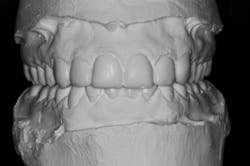

We digitally analyze our esthetics and smile design using the Dawson Diagnostic Wizard (the Dawson Academy). One of our biggest esthetic concerns in this case was caused by a functional issue. As you can see in the photos (figures 1 and 2), the patient has significantly more attritional wear on the right side versus the left. Due to the wear, the right anterior teeth have suffered from more compensatory eruption than the left, which results in uneven gingival architecture and esthetically displeasing length-to-width ratios of the anterior teeth (figures 3 and 4).

When we start to look at our occlusal shots (figures 5 and 6), it is obvious that we have some acidic erosion into dentin as well as significant wear facets from attrition. The pulp chambers of teeth Nos. 8 and 9 are now visible due to the loss of lingual tooth structure.